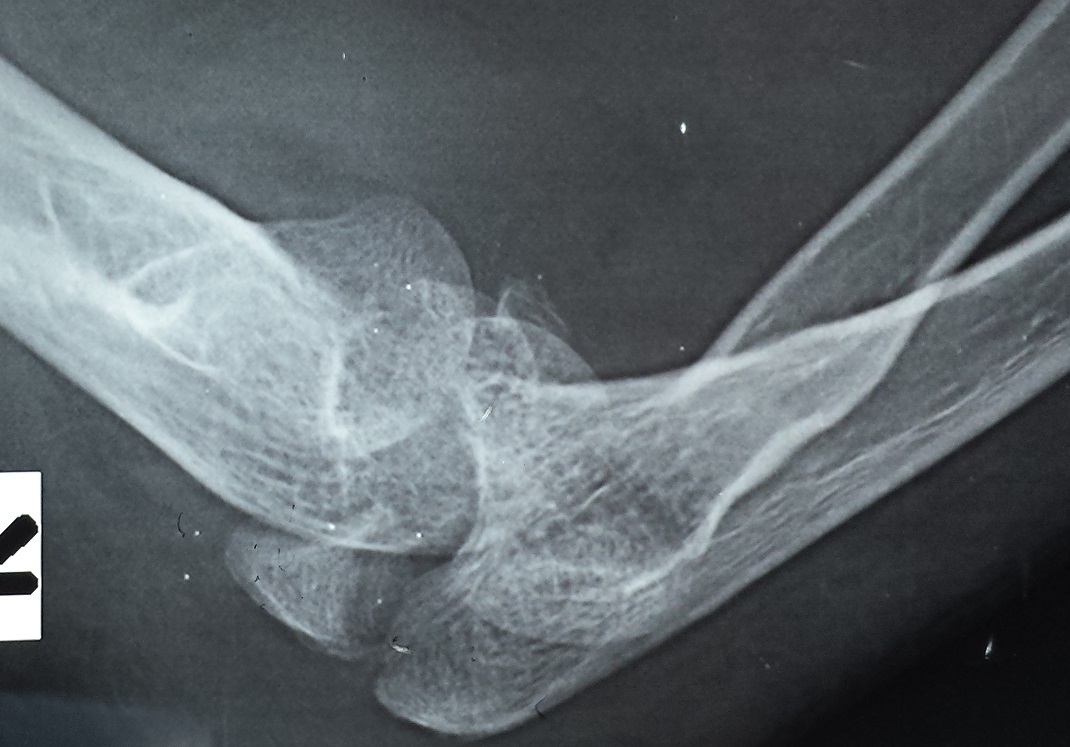

From www.orthobullets.com

Elbow Dislocation Trauma Orthobullets Elbow Support After Dislocation You will see a specialist in the fracture clinic 1 to 2 weeks after your injury. Recovery time after an elbow dislocation can vary. Elbow dislocations can be complete or partial, and usually occur after a trauma, such as a fall, motor. When the joint surfaces of the elbow's three bones are separated, the elbow is dislocated. The total time. Elbow Support After Dislocation.